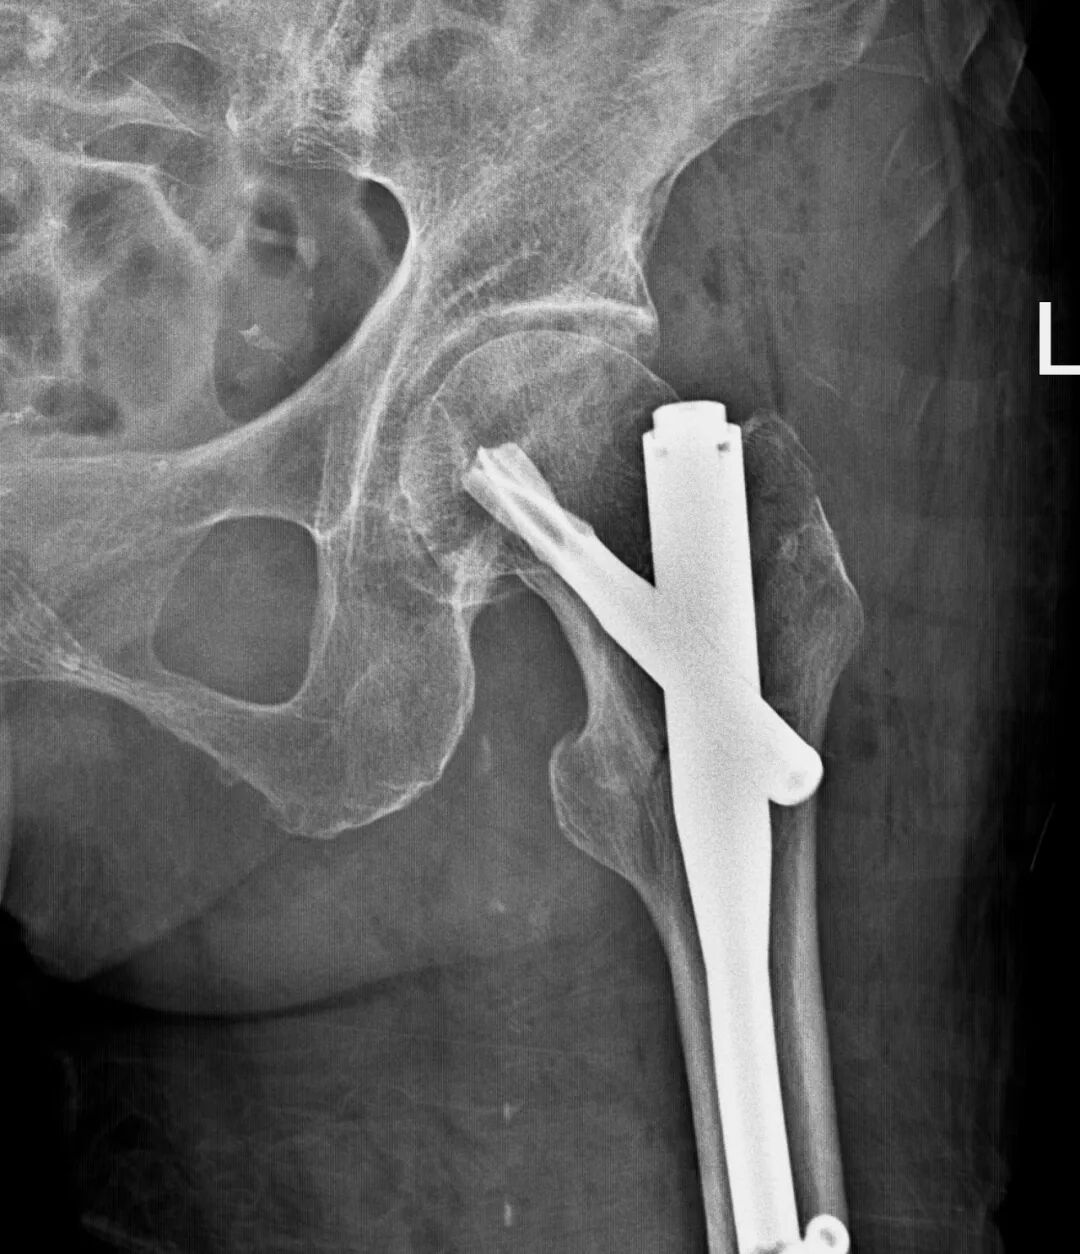

术前,转子间骨折

术后,骨折固定完美

近日,红阳医院外科,在手术室麻醉医师的配合下,为一位96岁高龄的老奶奶进行了左侧股骨转子间手术内固定术。麻醉过程顺利,手术成功。